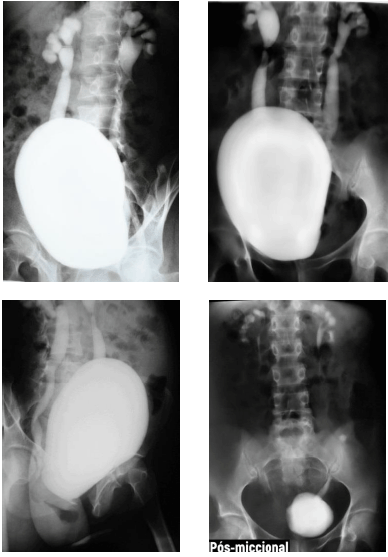

Criança de cinco anos de idade realizou exame contrastado de uretrocistografia miccional, que evidenciou os achados demonstrados nas imagens precedentes.

Acerca dos exames contrastados e das alterações do trato urinário na infância, julgue o próximo item.

A uretrocistografia miccional, além de identificar a presença de refluxo vesicoureteral, tem a capacidade de avaliar o grau do refluxo, que, no paciente em questão, é classificado como grau II.